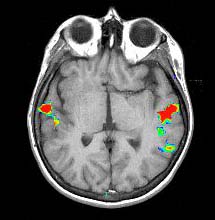

| Activation |

This paradigm elicits activation of the superior aspect of Broca's and Brodman's 37 areas. Some activation appears in parasagital parietal areas. The color in the left pterional fossa is due to vascular inflow. |